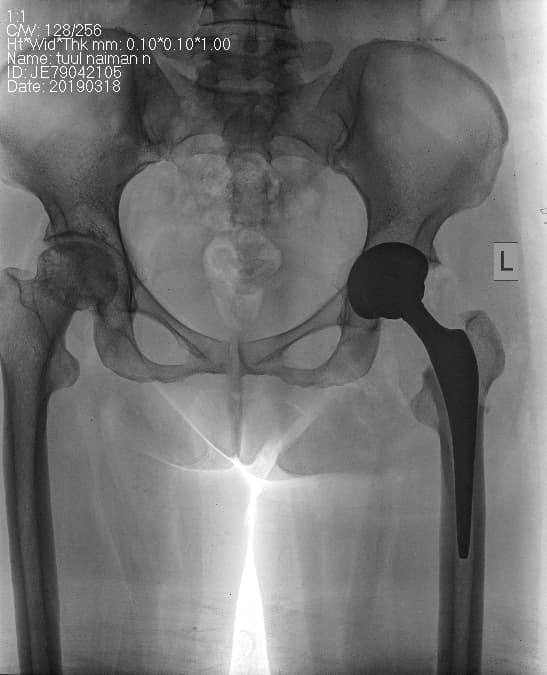

Түнхний үений төрөлхийн мултрал дутуу хөгжилтэй өвчтөний мэс заслын өмнөх болон дараах рентген зураг

Түнхний үе бүтэн солих мэс засал (THA) image3Түнхний үе бүтэн солих мэс засал (THA) image4